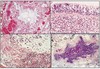

What type of tumour are these images? Describe why.

Squamous cell carcinoma

- Keratin at the top

- Intracellular bridges - parallel lines between cells

- Swirls of keratin

What type of tumour are these images? Describe why.

Adenocarcinoma

- Mucin stain with glands - show up blue

- Dark irregular nuclei still froming gland-like structure

What type of tumour are these images? Describe why.

Normal glandular epithelium with crypts